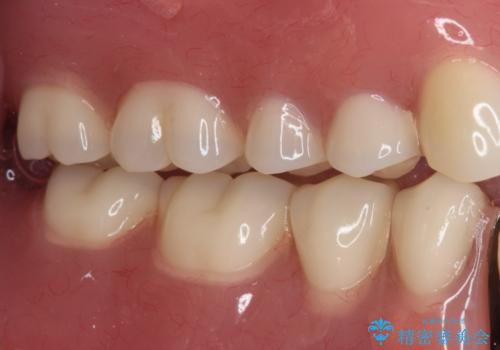

どこで咬んでいいのか分からない インプラント・オーバーデンチャーによる補綴治療

- どこで咬んでよいのか分からないとのことで来院された患者様です。

歯冠の崩壊した奥歯と、前歯の一部でした咬み合うことができず、入れ歯も試したものの、装着することができなかったようです。

全顎的にインプラント補綴を行うことも検討しましたが、費用面から、インプラントを土台とした入れ歯(インプラント・オーバーデンチャー)による補綴治療を行うこととしました。